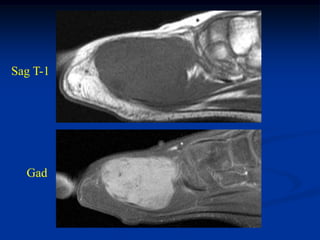

Case #251.1                   Desmoid tumor of foot

10 year male with firm tender swelling in forefoot 18 mos

following a pellet gun injury to foot

Cor T-1   T-2   Gad

Sag T-1

Gad

Axial T-1   T-2